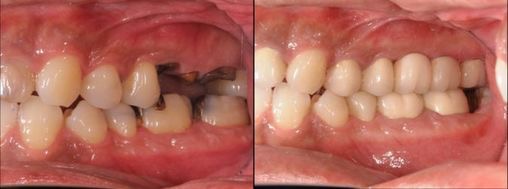

実際の症例、欠損部を放置していたことで

対合歯が挺出、理想的な形態に修正しセット。